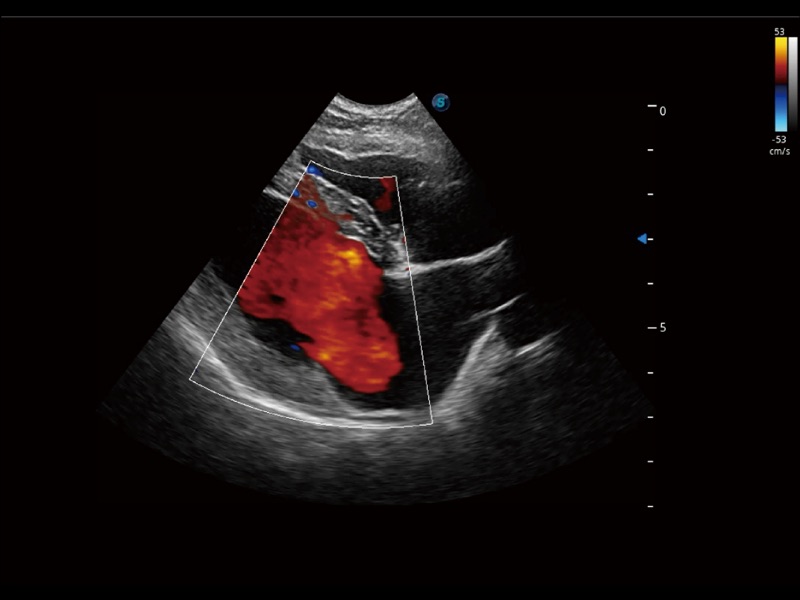

通过色彩血流和实时宽景相结合,可观察到完整的静脉或动脉的血流,方便医生检查。实时扫查过程中,如有任何操作失误也可以很容易地进行回扫擦除,而不会中断扫查。

通过创新的 Matrix E自适应滤波器和超长时间域算法,极大提升超低速微细血流的检出能力,同时更精准地滤除软组织和噪声信号,为兽用医生提供以往无法通过常规血流获得的疾病诊断信息。

采用红、橙、黄、绿、青、蓝、紫这七种肉眼最为敏感的色彩,直观地显示组织内血流灌注的时间先后信息,更精准捕捉血流灌注走行细节。